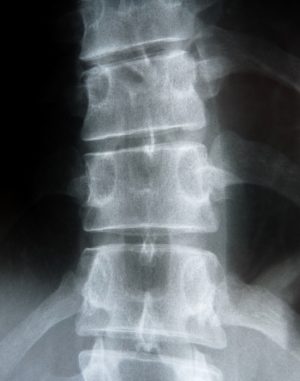

Das Gesetz verlangt, Menschen nicht unnötig ionisierenden Strahlen auszusetzen. Jede unnötige Strahlenexposition ist auch unterhalb der gesetzlichen Grenzen zu vermeiden (§ 28 der Strahlenschutzverordnung). Beim Röntgen wird die Hand der Strahlung ausgesetzt. Gibt es dadurch ein Risiko für die Gesundheit des jungen Menschen?

Bei dieser Maßnahme wird die Hand mit einer Strahlendosis von ca. 0,1 Milli-Sievert beaufschlagt — ist das nun viel oder ist das wenig? Hier drei Vergleiche, um diese Strahlendosis einordnen zu können:

- Bei einem Flug von Deutschland in die westlichen Regionen der USA oder nach Japan über die Polarregion hinweg werden die Menschen im Flugzeug ebenfalls einer Strahlendosis von 0,1mSv ausgesetzt, und zwar mit dem GANZEN Körper, und nicht nur mit einem Teilbereich wie z.B. der Hand [1].